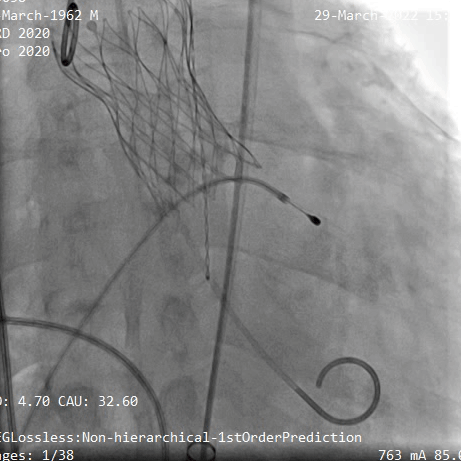

TaurusElite输送系统轻松过弓、跨瓣,AV29瓣膜瓣环下0mm定位释放,到工作位后造影显示瓣膜形态、位置良好

瓣膜定位

释放到工作位观察

释放脱钩后瓣膜形态、位置良好,冠脉血流灌注正常,无瓣周漏,弓部血管造影未见异常

术后根部造影

术后弓部血管造影